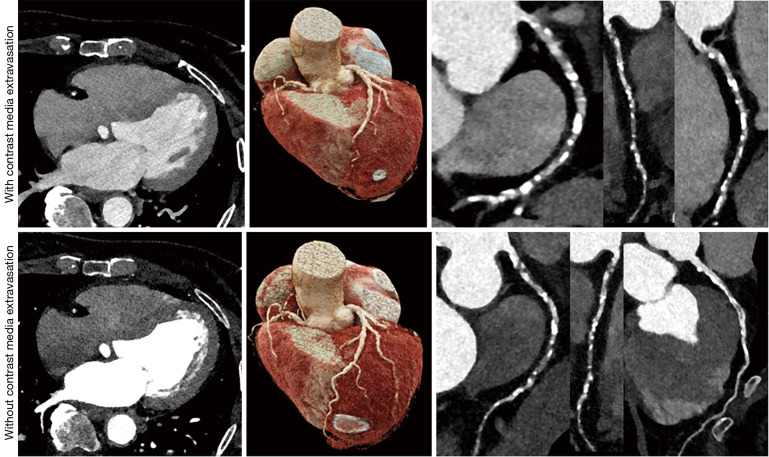

背景:造影剂(CM)被广泛应用于对比增强计算机断层扫描(CECT),以增强异常结构的可视化。CM外渗是一种公认的并发症,可引起轻度肿胀或严重损伤(如溃疡、坏死)。目前对严重外渗的研究仅限于病例报告或缺乏对危险因素的大队列分析。本研究旨在通过大规模临床数据探讨轻度和重度CM外渗损伤的危险因素,验证发病率和结局,并比较患者/技术/CM相关因素,以帮助早期识别和预防。方法:回顾性队列研究。在2012年11月至2023年12月期间,同一家机构在CECT扫描期间共进行了586812次CM注射。其中,709例,男334例,女375例;年龄:62.9±15.2岁),CM外渗损伤。外渗损伤按严重程度分类。研究不同程度损伤的发生频率和临床结果。采用logistic回归和广义估计方程分析对严重损伤的危险因素进行评价。结果:CM外渗占0.12%(709/586,812)。709例外渗伤中,轻度672例(94.8%),中度32例(4.5%),重度5例(0.7%)。只有5名患者接受了皮肤科医生或烧伤专家的咨询,没有人需要手术。多因素分析强调糖尿病的存在[DM],优势比(OR) =8.04;结论:CM外渗损伤多为轻度,无严重后果。已经确定了严重CM外渗损伤的多个可改变的危险因素,可以减轻损伤的严重程度。